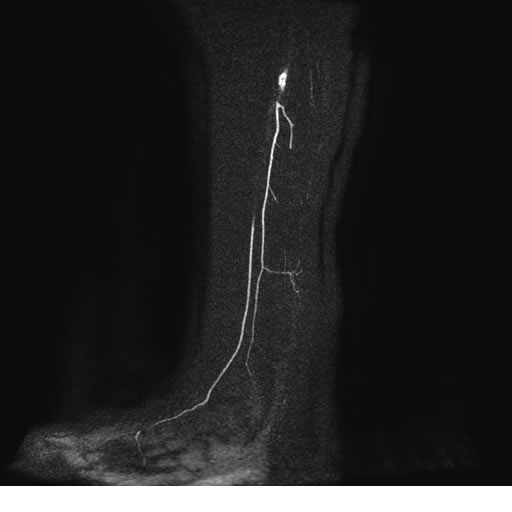

Se realiza estudio de MRI de pierna izquierda, utilizando secuencias Spin Echo y GRE en diferentes planos, se realiza angio MRI en fase arterial y venosa de pierna izquierda

El estudio demuestra masa a nivel de los músculos gemelos, más evidente en secuencia con pulso de saturación de grasa, en el estudio de angio resonancia de pierna la fase arterial no muestra ninguna anormalidad, en la fase venosa se observa acumulo del medio de contraste a este nivel.

Se concluye que se observa una masa de tejido muscular sumamente vascularizada compatible con un hemangioarcoma.